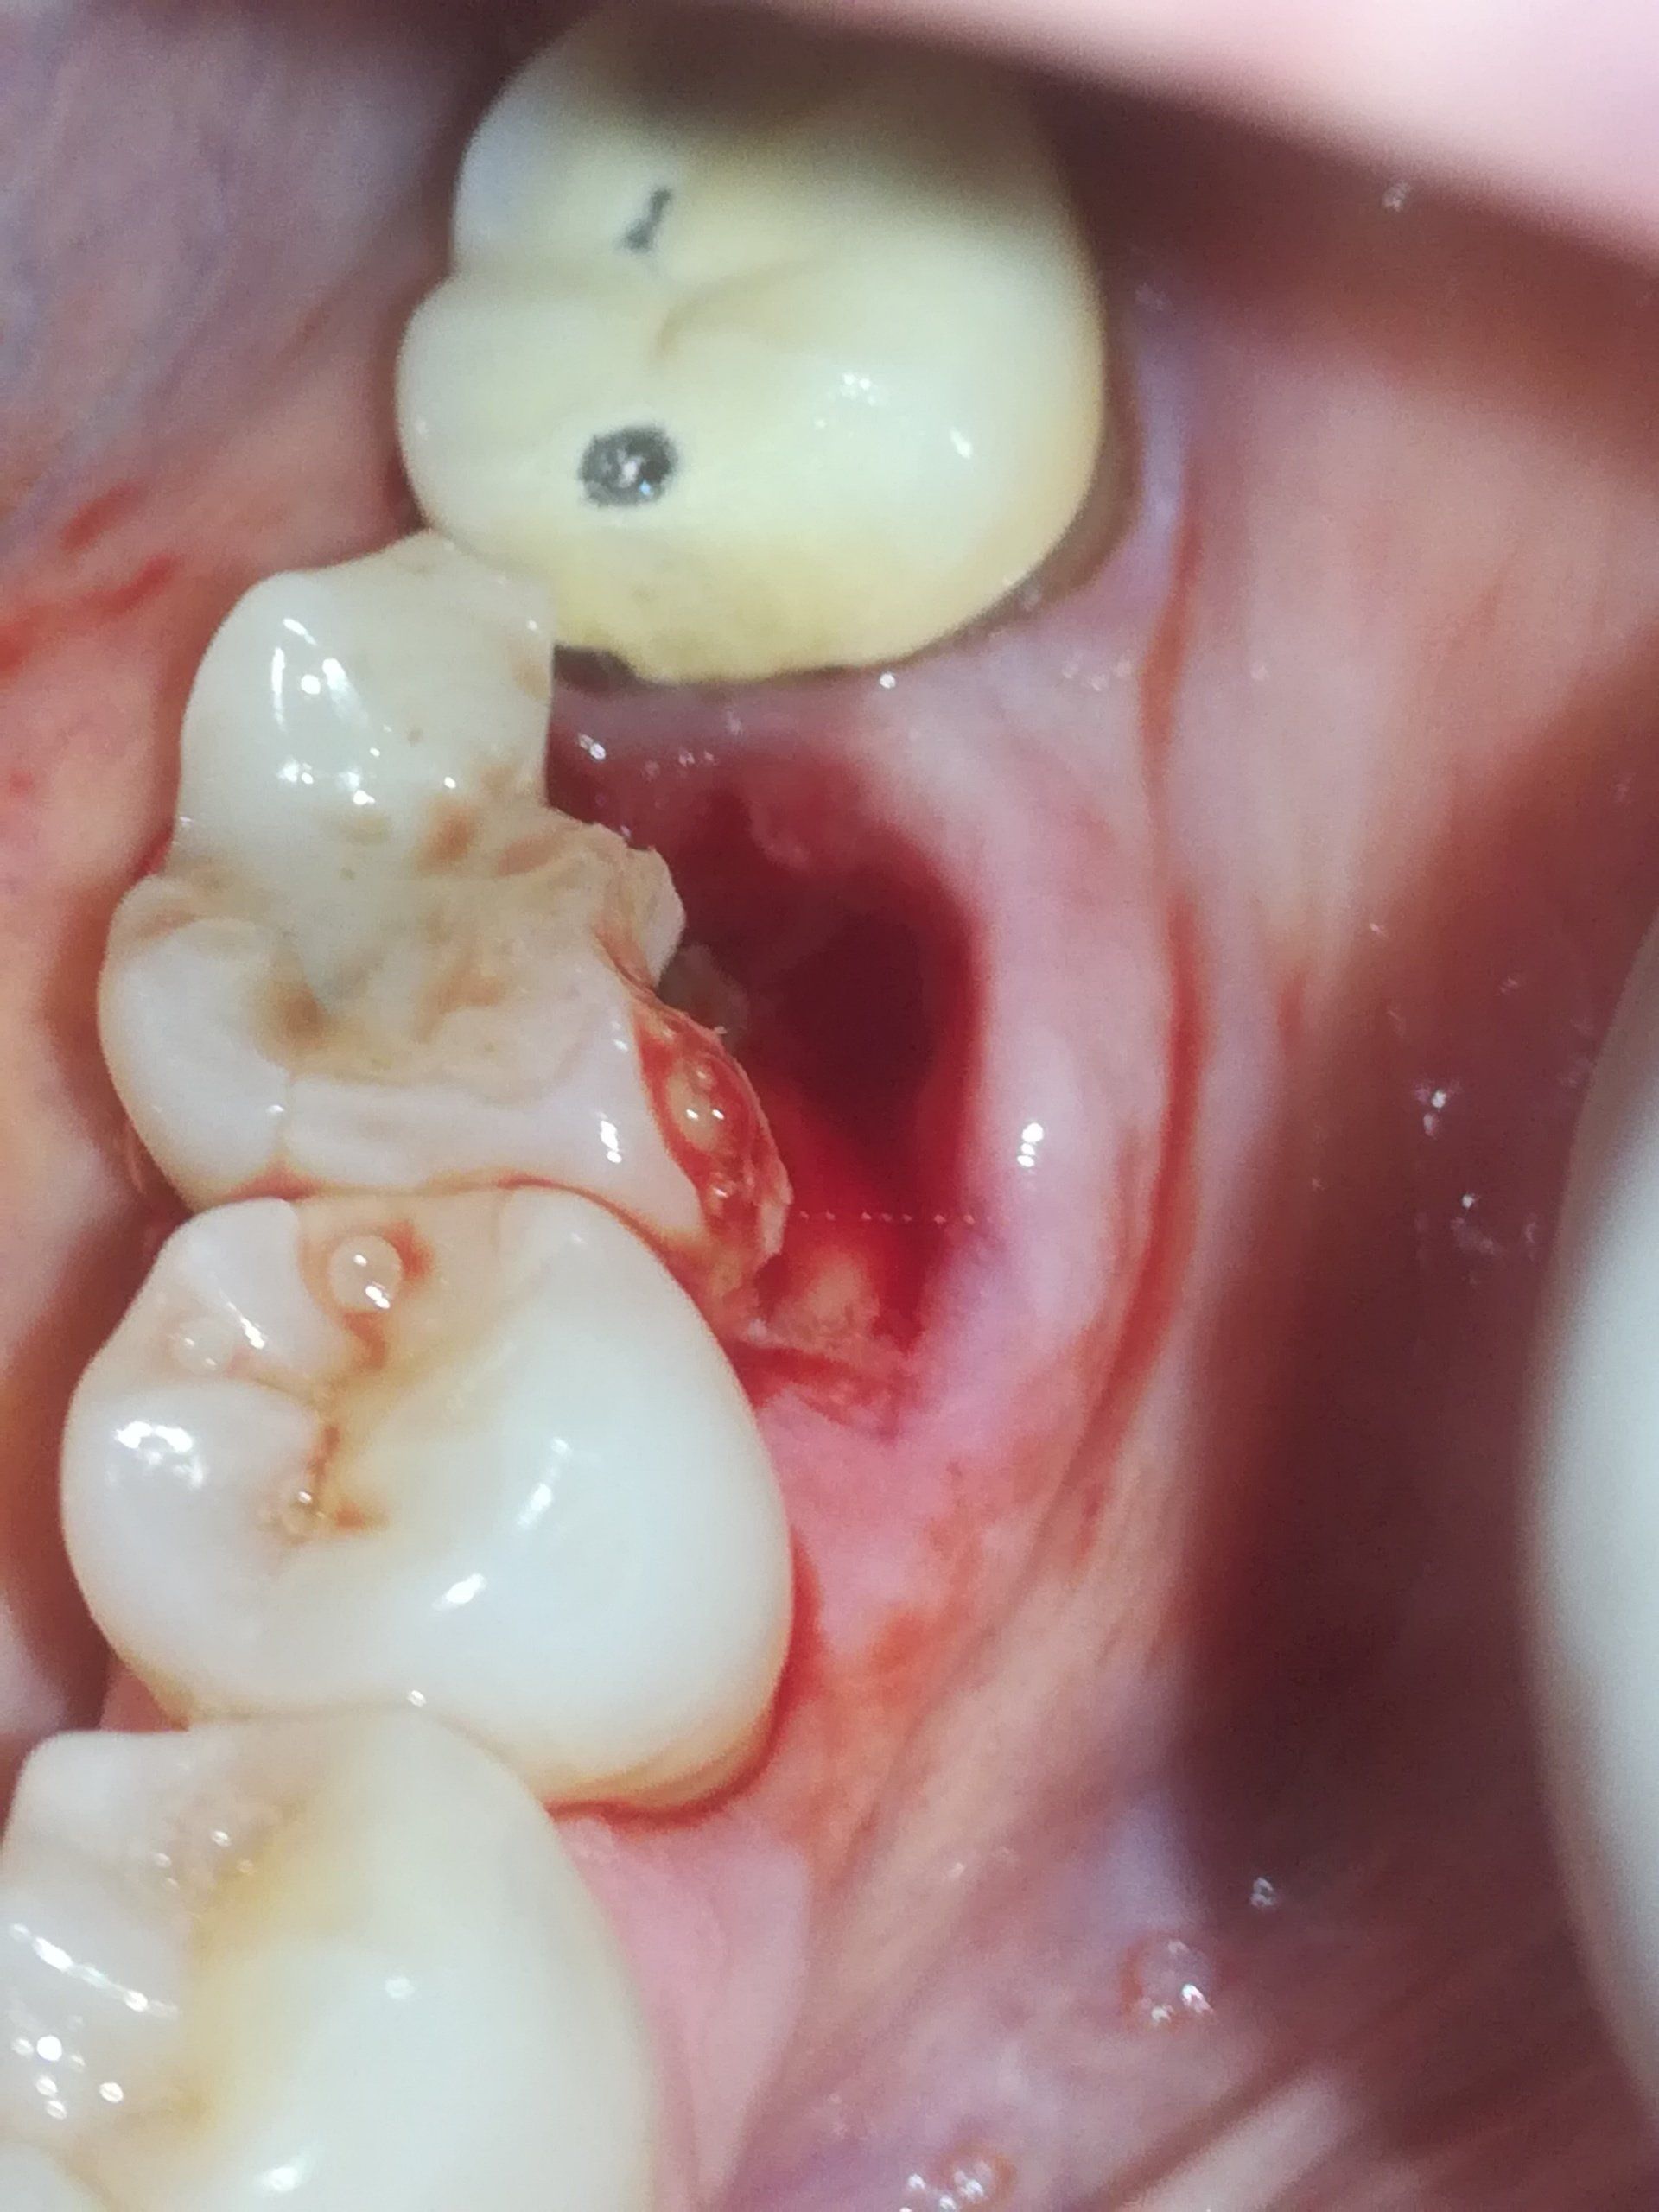

Comunemente chiamata “capsula”, la corona è una protesi fissa che viene adottata nel caso di denti molto danneggiati, rotti o indeboliti (a seguito di trattamento endodontico o problemi occlusali) al fine di ricostruirli, proteggerli e rinforzarli. Il compito della protesi è quello di sostituire l’originale corona dentale ,ovvero la parte visibile e più esterna di un dente.